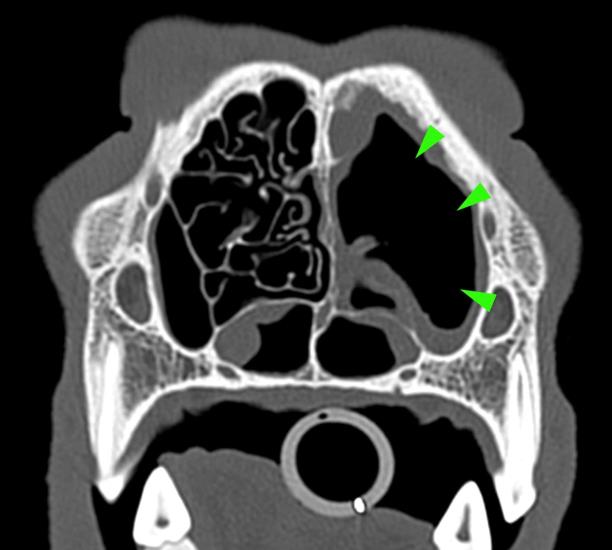

Diagnostic imaging is a pivotal part of the diagnostic process, narrowing down the likely causes of disease and allowing clinicians to understand the best way forward in achieving a definitive diagnosis and treatment plan.

Whether it’s assessment of acute or chronic disease including staging of cancer patients, or pre-surgical evaluation, the work of the team is crucial. Our expert team investigate all manner of conditions affecting any part or system of the body, from the bones to the brain.

Imaging is frequently used to guide biopsies of diseased organs that are otherwise inaccessible, or to find and retrieve foreign bodies. Both applications are extremely useful and can avoid the need for more invasive surgery.